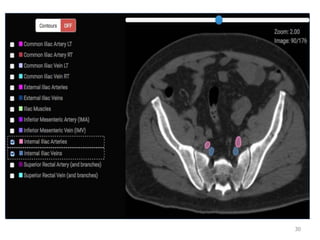

• Now turn off ALL contours

• Start at abdominal aorta

• Scroll inferiorly, following

branches

• Lymph nodes sit on vessels.

This is why we contour

vessels in nodal CTV

• Sequence of vessels:

– Aorta (artery) or IVC (vein) 

Common Iliacs (R and L) 

Internal iliac (go posterior/in

front of sacrum) and External

Iliacs (go anterior  become

inguinal/femoral when exit

pelvis)

27

Review anatomy of pelvic vessels